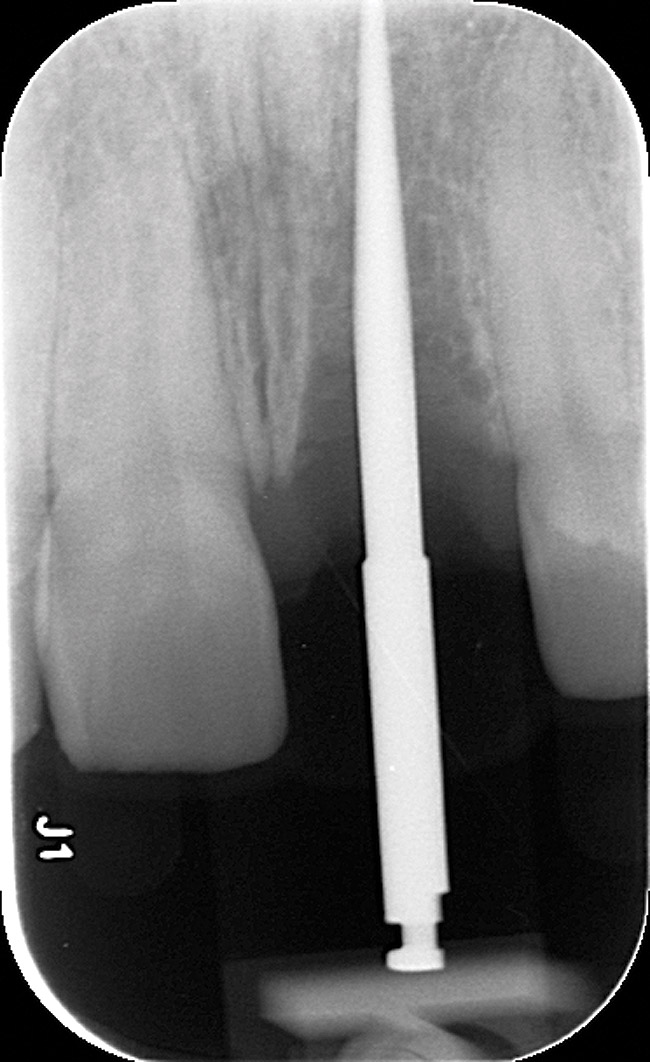

Radiographic evidence of external root resorption on tooth No. 26 and periapical radiolucencies with a history of prior endodontic treatment, including apicoectomies, were present on the mandibular central incisors (Figure 2).

Figure 2  Initial periapical radiographs showing failed endodontic treatment of Nos. 24 and 25, and root resorption, No. 26.

Figure 2